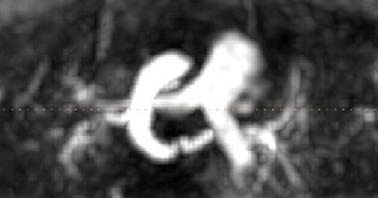

En la Resonancia Nuclear Magnética de arco aórtico (secuencias SShot , T1 spin echo, y ecoplanares axial y coronal) , y en el estudio angiográfico con gadolinio, se objetivó un malformación vascular, correspondiente al arco aórtico derecho y la arteria subclavia izquierda aberrante que junto con el ligamento arterioso, conformaban una estructura anular alrededor del esófago. (Figure 3)

Figura 3. Resonancia Magnética Nuclear